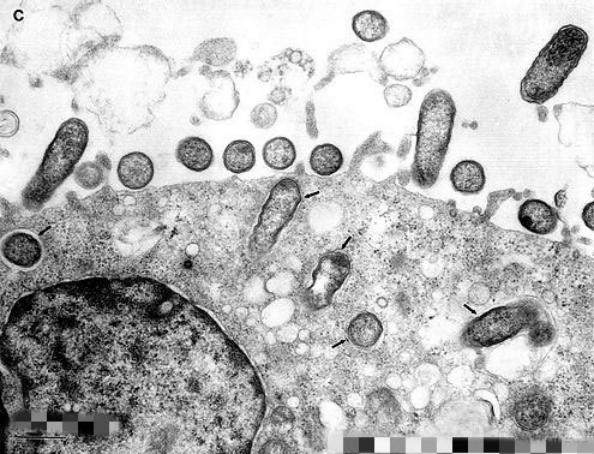

然而,直到调查的第二年,霍华德和他的助手J.J.Moore才取得重大突破,他们发现木蜱是引起发烧的芽孢杆菌的主要携带者。霍华德将病人的血液注入荷兰鼠体内,即引起了感染,同时他也发现实验发现木蜱的叮咬也能将这种病传染给了荷兰鼠。通过显微镜观察,霍华德发现患病动物的血液中有致病的球杆菌,这种球杆菌后来被叫做立克氏次体。